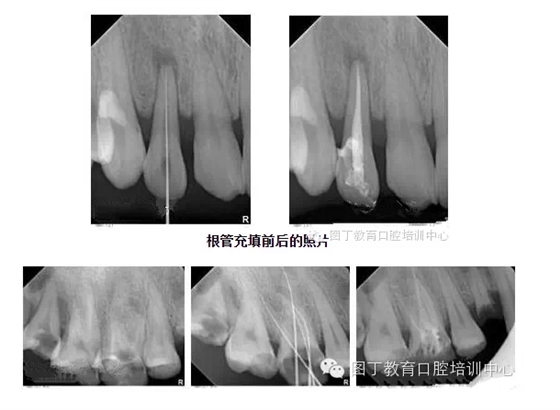

根管充填

總結(jié)幾個要點:

1,根管充填到位的前提是根管要預(yù)備好;

2,把握好充填長度;

3,選擇合適的主膠尖意義很大——合適的主尖其尖端恰好封閉根尖孔;

4,糊劑適量即可,因為充填的主體是牙膠。

5,側(cè)方加壓后的垂直加壓不可忽視,因為通過垂直加壓后的充填體更嚴(yán)實。